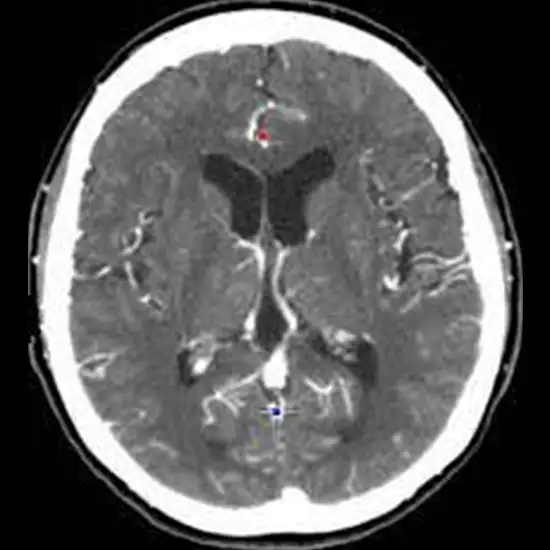

A CT Head Plain and Contrast is an imaging procedure that is used to assess the structures of the brain, face, and sinus to detect various disorders and the existence of pathology.

For CT Head Plain, contrast media is not used. It is also known as a Non-Contrast CT Head.

For CT Head contrast, the contrast media is given to the patient for better visualization of and diagnosis of the problem.